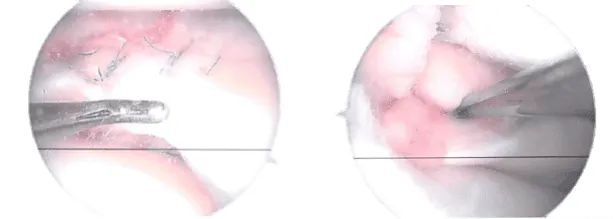

General anesthetic was administered. Over the right lower limb, a tourniquet was applied. Aseptically, the right lower limb was prepped and draped and Esmarch applied too. The knee joint was inspected and a lateral entry portal was established. A medial meniscus peripheral rupture was discovered.

A grade 1 to grade 2 median condylar osteochondral lesion of the femur was also found. The ACL had some fraying and degeneration. the healing of the medial meniscus. Sutures from Fast-Fix were used. The peripheral laceration from the posterior horn to the mid body was repaired with seven sutures.

Actual Arthroscopic images taken during the operation